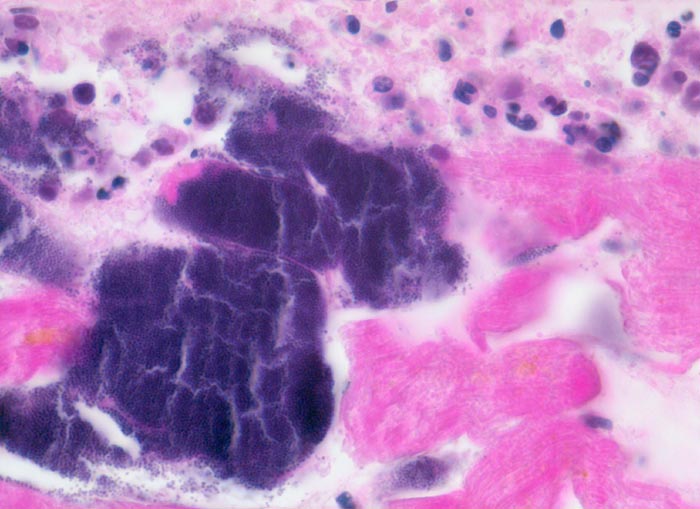

Morphologische Merkmale:

• Blaue Flecken in der Übersicht. Diese entsprechen Ansammlungen von neutrophilen Granulozyten (Mikroabszesse).

• Links unten im Bild sind mehrere Arterien mit intra- und perivaskulären Kokkenbakterien und neutrophilen Granulozyten erkennbar.